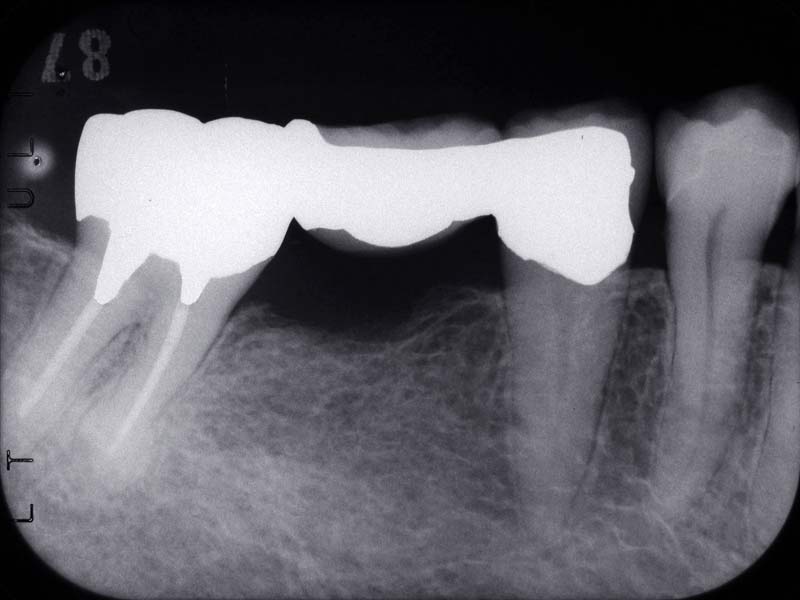

入れた歯の噛み合わせがおかしい、物がよくはさまる、糸楊枝が引っかかるなどの経験をしたことのある方も多いと思います。これは金属の被せ物や詰め物の精度の問題です。下の左右のレントゲン写真を比べてみましょう。レントゲンの中で白く抜けているのは金属の詰め物です。左側のレントゲンの詰め物は自分の歯と合っていないのがわかります。治療後の右側レントゲンの詰め物は歯とピッタリ合っているように見えます。糸楊枝を入れてもどこも引っかかりませんし違和感もありません。いつもこのように製作することが理想ですがそのためには衛生士が歯と歯肉をきれいにし、歯科医がきれいに歯を削り、歯形を取り、技工士が丁寧に補綴物を製作というすべてのステップをしっかり行うことが必要です。コストも労力もかかることですが須貝歯科医院ではすべてを院内で行うことで精度の高い物を作るように努力しています。残念なことですが現在の保険診療では完全な赤字部門で院内で賄うことで何とか頑張っています。保険で使用できる金属があまり良い物ではないこともあり、できるだけ保険外の適切な材料を使用して被せ物や詰め物を作っていただけるように患者さんにはお願いしています。

当医院で製作したブリッジですが糸楊枝を入れてもどこも引っかかりません。いつもこのように製作することが理想ですがそのためにはきれいに歯を削り、歯形を取り、丁寧に補綴物を製作というすべてのステップをしっかり行うことが必要です。 コストも労力もかかることですが須貝歯科医院では補綴物にこだわり精度の高い物を作るように努力しています。